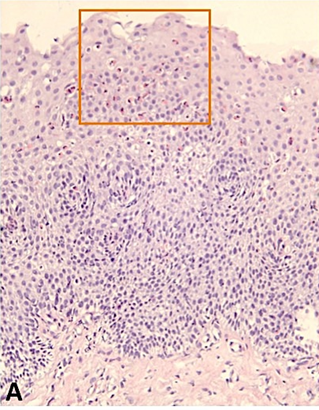

Комментарии: Патологоанатомическое исследование включает осмотр биоптатов, окрашенных гематоксилином и эозином с подсчетом количества эозинофилов при большом увеличении (х400) [1,21,117,124,125]. Главным критерием установления диагноза ЭоЭ служит интраэпителиальная эозинофильная инфильтрация с количеством эозинофилов в поле зрения микроскопа при большом увеличении – 15 и более (или ≥ 60 эозинофилов на 1 мм2) (приложение А3: рисунок 2а).

Дополнительными гистологическими критериями ЭоЭ являются эозинофильные микроабсцессы, гиперплазия базального слоя эпителия, расширение межклеточных пространств, расположение эозинофилов в поверхностных слоях эпителия, мастоцитарная и лимфоцитарная инфильтрация, удлинение сосочков и фиброз собственной пластинки слизистой оболочки (приложение А3) [1].

Патологоанатомическое исследование включает осмотр биоптатов, окрашенных гематоксилином и эозином. Главным критерием установления диагноза ЭоЭ служит интраэпителиальная эозинофильная инфильтрация с количеством эозинофилов в поле зрения микроскопа высокого разрешения 15 и более при увеличении х 400 (или ≥15 эозинофилов/0,3 мм2 или >60 эозинофилов/мм2) [116].